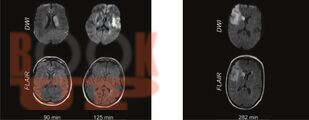

В учебнике представлены основные сведения по частной клинической неврологии, входящие в программу изучения дисциплины в медицинских ВУЗах. Изложена базовая информация и новейшие научные сведения об этиологии, патогенезе, клинике, диагностике и лечении наиболее значимых и распространенных заболеваний нервной системы в удобном для восприятия формате — в виде таблиц и блок-схем.

Учебник предназначен для студентов медицинских ВУЗов, обучающихся по специальности 31.05.01 «Лечебное дело» и 31.05.02 «Педиатрия», будет полезен для ординаторов, аспирантов, изучающих неврологию и нейрохирургию, врачей неврологов, терапевтов, педиатров, врачей общей практики и др.